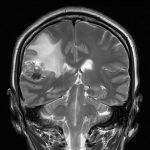

手術前1

手術前2